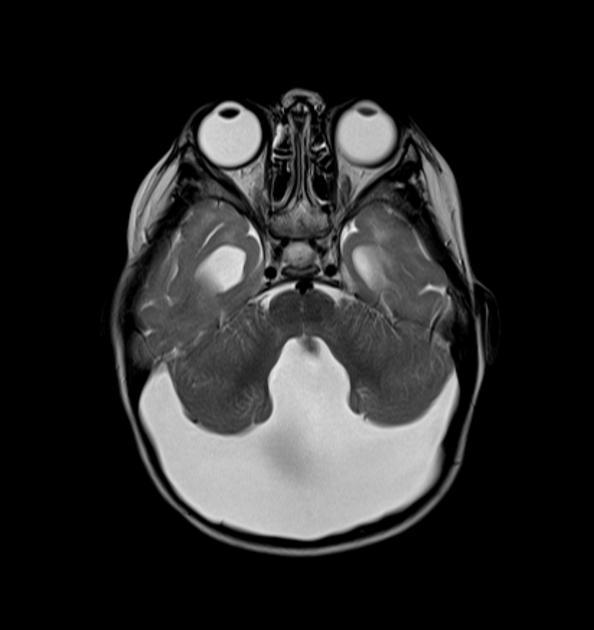

Diagnosis?

Imaging findings on CT and MR?

Canavan disease.

CT: diffuse low attenuation in cerebral and cerebellar white matter.

MRI: High T2 and low T1 in the white matter. Predominantly affects the sub-cortical U fibers, worst in the occipital lobes, then frontal/parietal. Thalami and basal ganglia affected in severe cases. Relative sparing of the internal capsule. MRS: may have increased NAA peak.